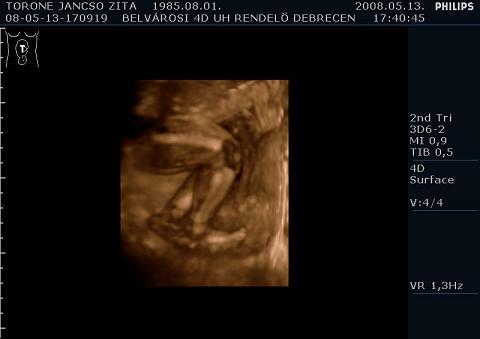

Tegnap voltunk a 4D-n.... háááát meg kell mondjam hogy a kis Patríciánk ténleg nagy meglepetést akar szerezni nekünk mert most még anyit sem muttott meg magából mint a múltkor!!! Mondtam is a hölgynek hogy ránk tutira emlékezni fog és majd be viszem neki Patrícit és megmutatom ha megszületett hogy lássa miröl maradt le!

De rá jöttünk hogy a Lézerbe jobb minőségü a gép és valszeg ott jobban látszott volna, de ez van. Igy is jó volt.

Nagyon ki huncut lányod lesz, h ennyire nem mutatja meg magát! Én már azt sem tudom akkor h melyik 4D rendelőbe menjünk, abban biztam, h azt fogod mondani majd erre h jó volt. Mennyire van különbség a kép élességében szerinted? Azt nem lehetett volna vhogy állítani? De a dvd felvétel jó lett??